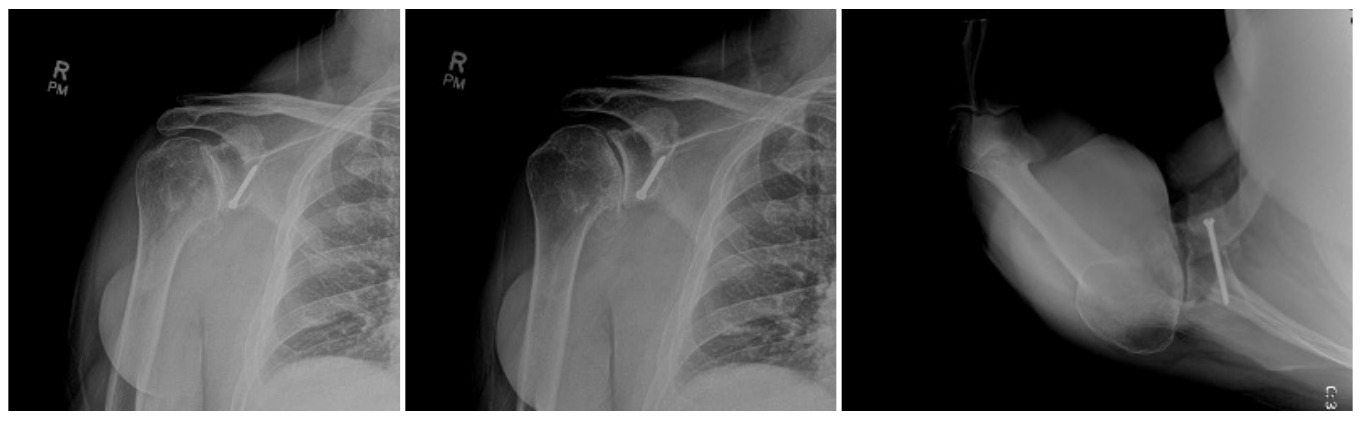

Case one is a 58-year-old male who is an avid golfer with long standing right shoulder pain. Surgical history includes previous Bristow procedure 30 years prior. Current Subjective Shoulder Value (SSV) is 30% and pain is 8/10 at baseline. Active range of motion was 110° of forward flexion, -10° of external rotation and interna rotation to the lateral buttock. Radiographs (Figure 1) and computed topography (CT) scan (Figure 2) show retained implants with loss of joint space, glenoid retroversion, and significant posterior humeral head subluxation. The patient had failed conservative management and was indicated for arthroplasty. Due to significant posterior bone loss and retroversion, an augmented anatomic component was selected for this patient. Radiographs at one year show a well seated glenoid component with restoration of the joint line and a centered humeral head (Figure 3). At five years, SSV had improved to 95% with excellent clinical motion (Figure 4).